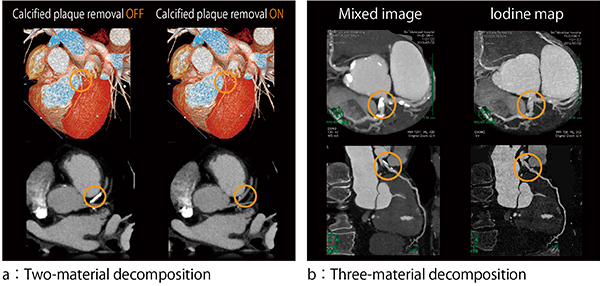

さらに,DEはステント内腔の評価や石灰化病変に対して応用されている。冠動脈のステントや石灰化領域の内腔評価は,X線CTの空間分解能の限界や拍動による動き,ステントや石灰化によるビームハードニングなどの影響のため正確な診断が困難とされている。特に,ステント内のプラーク性状評価については,ステント内腔壁の低濃度付着物を金属アーチファクトと混同しやすく,評価不能とされることも珍しくない。現在,DE Monoenergeticによる仮想単色エネルギー画像を用いることで,石灰化や金属からのアーチファクトと部分体積効果によるCT値の変動,石灰化・金属の膨張を抑えた評価が可能となっている(図2)。これにより,従来困難とされてきたステント内のプラーク性状評価について有用性が示されている5)。また,冠動脈の石灰化領域における内腔評価については,骨とヨード造影剤を識別するTwo-material decompositionアルゴリズムを用いる手法と,ヨード造影剤を抽出,定量化するThree-material decompositionアルゴリズムを用いることによって,ヨード成分から石灰化成分を分離することが可能である(図3)。いずれの手法においてもハードウェアの発展とともに着実に精度の向上を図っており,エビデンスの積み重ねと同時に,今後の冠動脈イメージングの多様化を期待させるアプローチとなっている。

図3 DEイメージングによる物質弁別を利用した冠動脈の石灰化除去

Two-material decompositionとThree-material decompositionのアルゴリズムを利用して冠動脈から石灰化を分離することができる。

a(画像ご提供:アメリカ・Medical University of South Carolina様)

b(画像ご提供:伊東市民病院様)